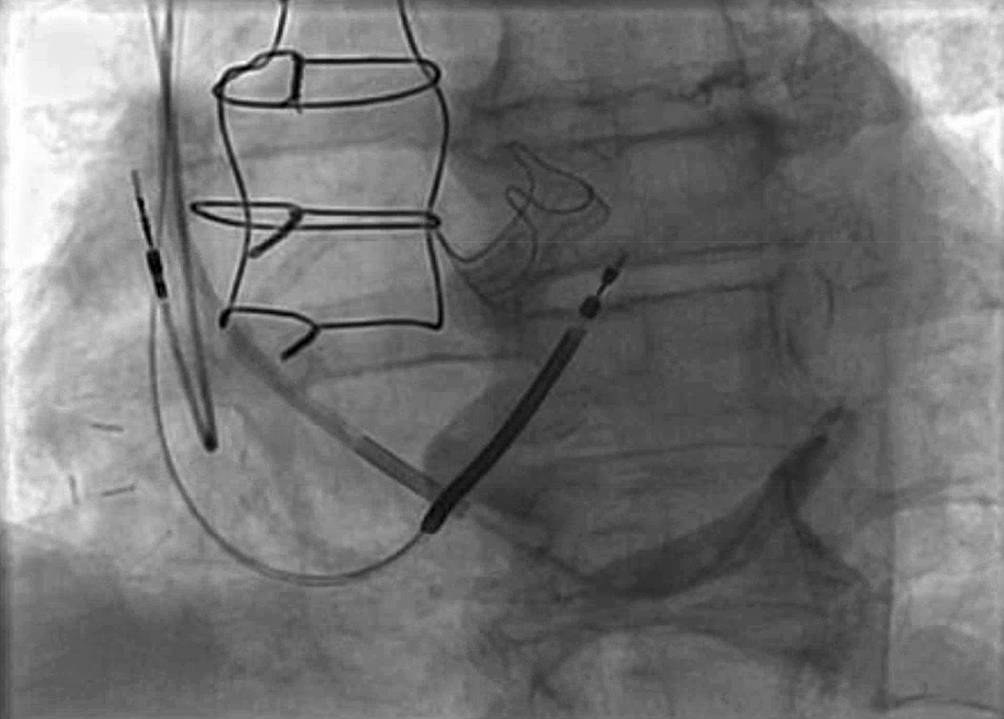

CRT verbessert die Herzfunktion, indem sie die ventrikuläre Kontraktion bei Patienten mit Herzinsuffizienz synchronisiert, insbesondere bei Patienten mit Linksschenkelblock (LBBB) oder anderen Formen elektrischer Dyssynchronie. Das CRT-Gerät umfasst typischerweise 3 Elektroden: eine im rechten Vorhof (RA), eine im rechten Ventrikel (RV) und eine im Koronarsinus zur Stimulation der lateralen Wand des linken Ventrikels (Abb. 1). Bei Patienten mit permanentem Vorhofflimmern (AF) kann auf die Vorhofelektrode verzichtet werden, und der entsprechende Anschluss am Gerät kann blind verschlossen werden.

Abb. 1

a Röntgenaufnahme des Thorax in p.-a., welches die 3 Elektroden eines CRT-Schrittmachers in loco typico zeigt. b Laterale-Thorax-Rröntgenaufnahme; die 3 Elektroden eines CRT-Schrittmachers liegen an typischer Stelle und die posteriore Lage der CS Elektrode wird deutlich